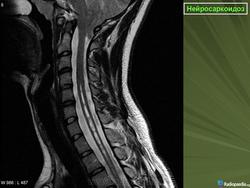

ID: 17921 Neurosarcoidosis Dr Frank Gaillard - 25 May 2012 The case demonstrates typical features of neurosarcoidosis, which are of...

Случай 5: вовлечение спинного мозга